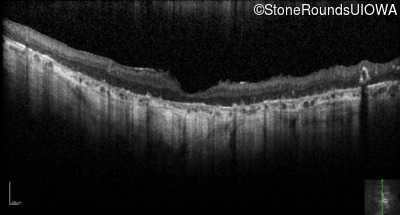

Optical Coherence Tomography - Right - Hand Motion

Exemplar / OCT Stack